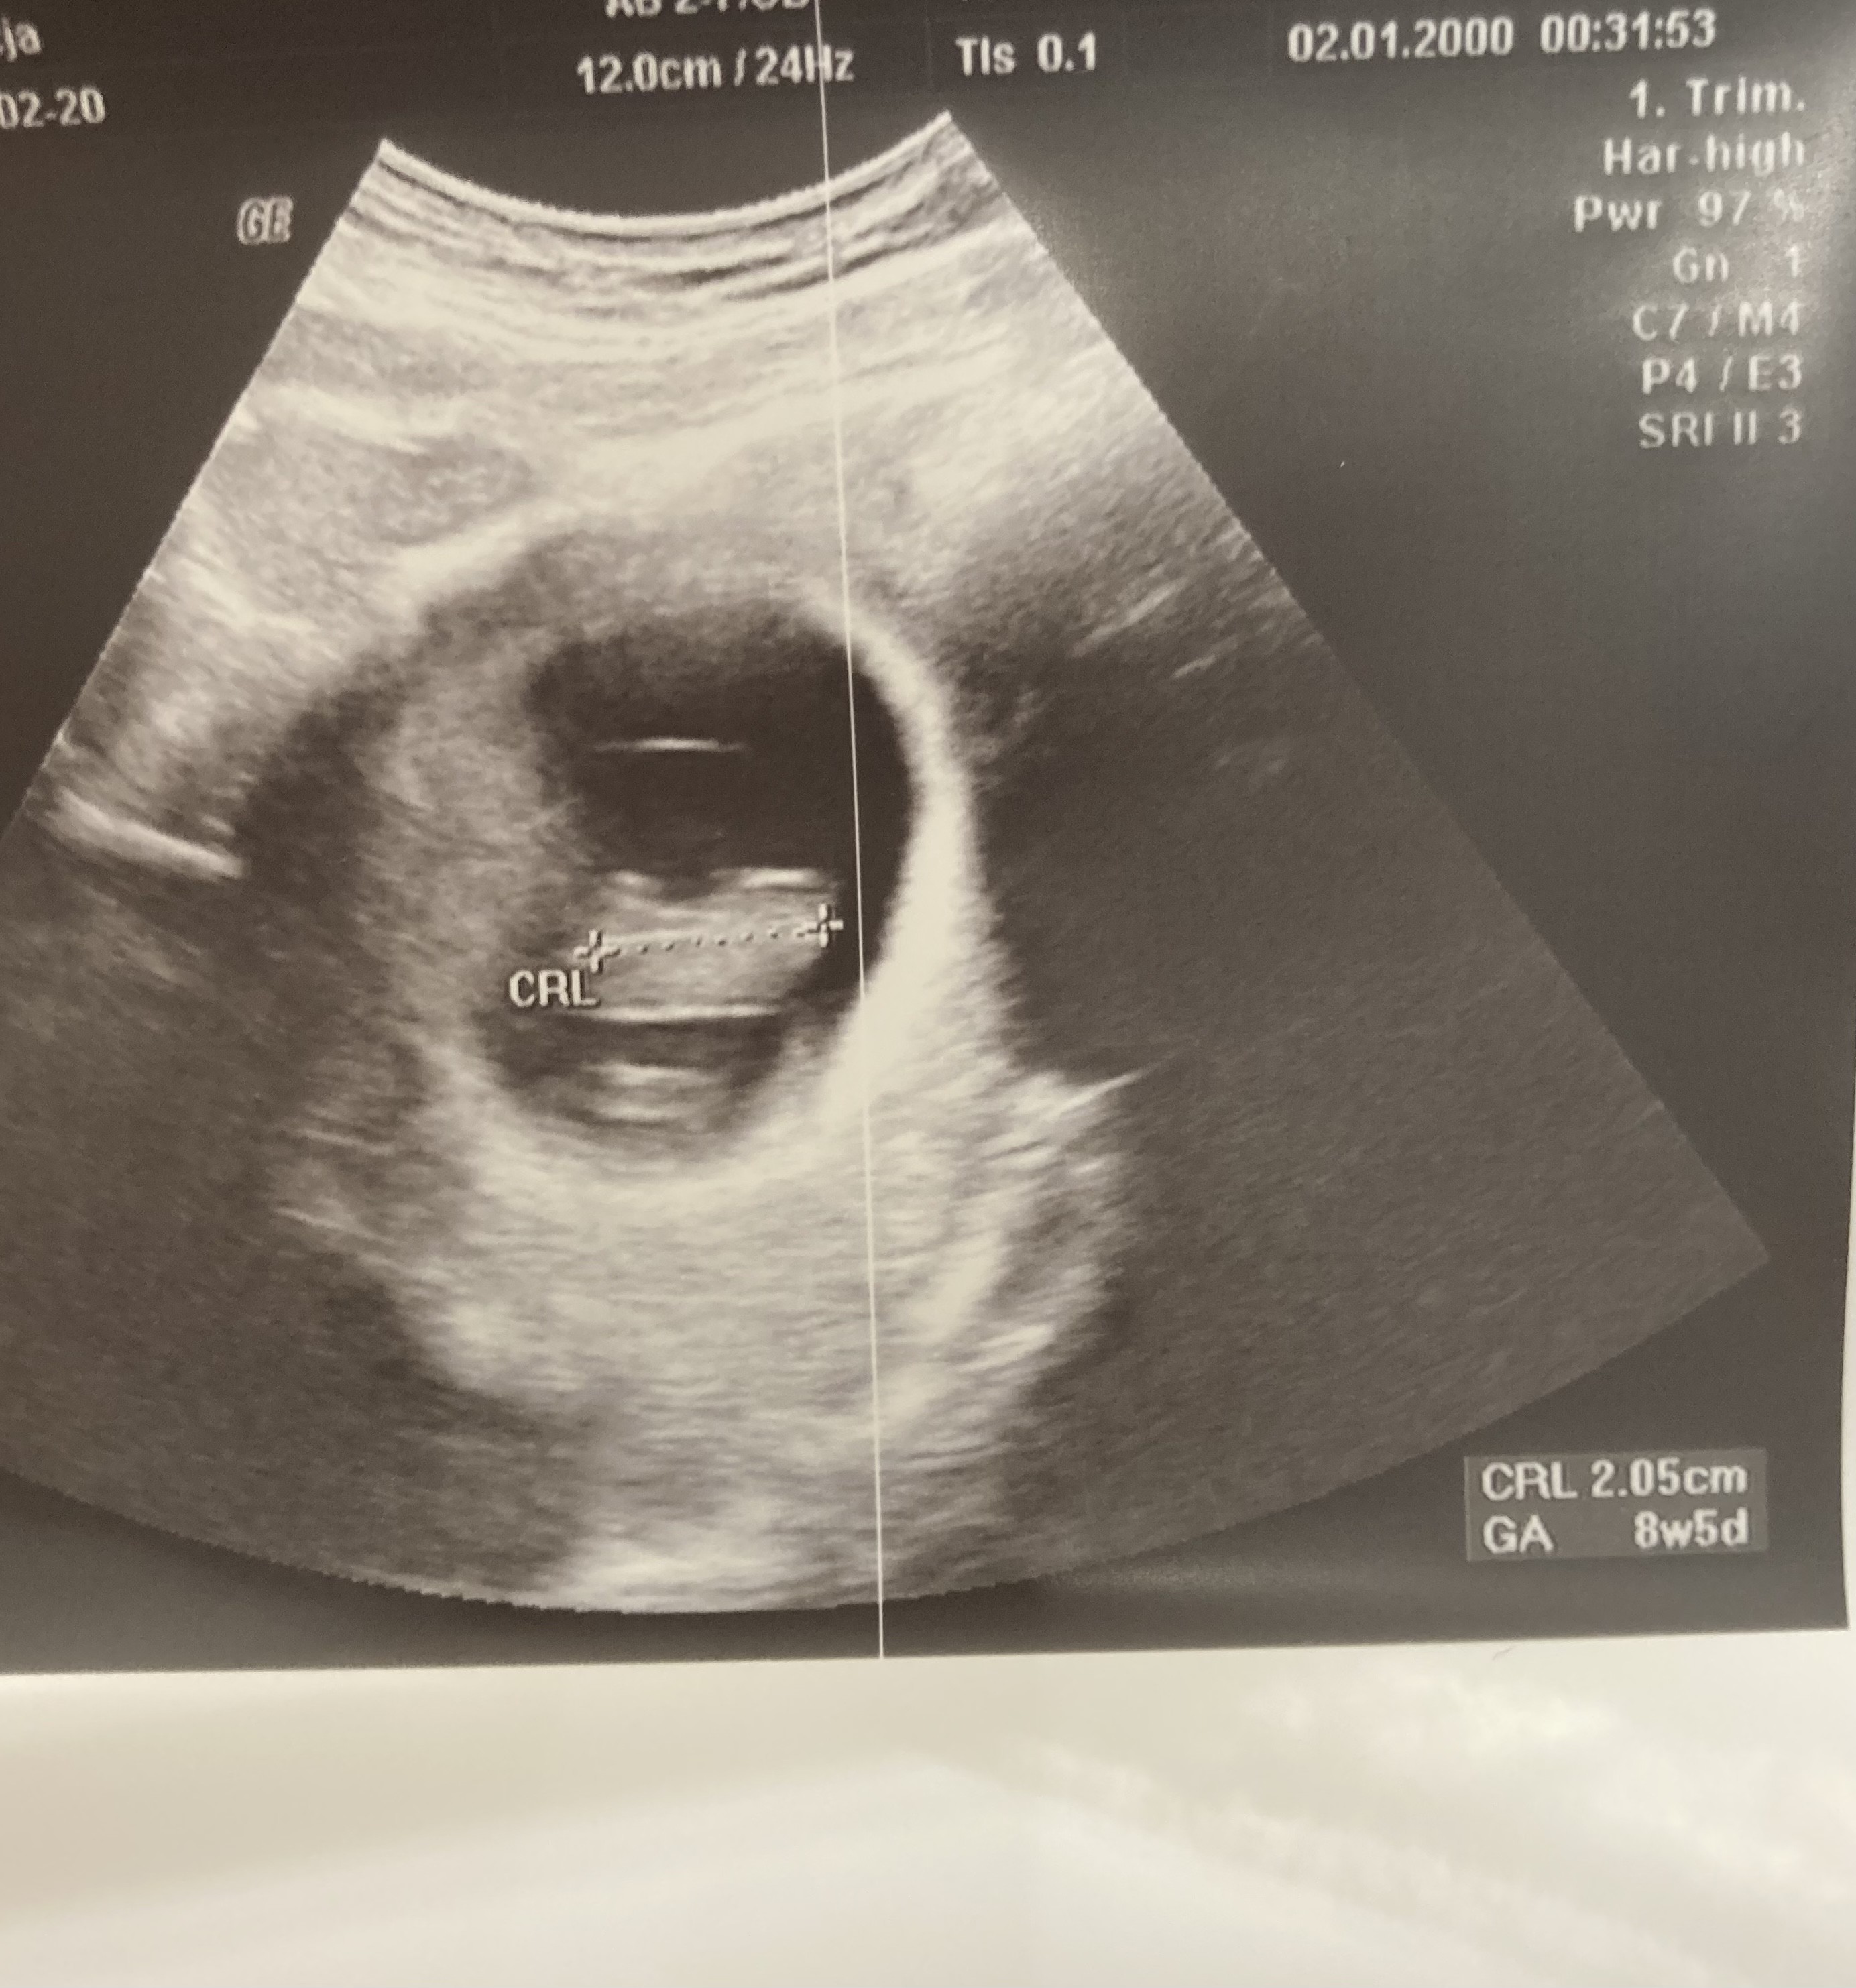

Ja właśnie jestem po wizycie, wszystko w porządku, tylko tarczyce muszę podreperować z endokrynologiem

maluszek już ma 2cm, wychodzi z usg 8+5. Serduszko bije 176 uderzeń- doktor powiedział ze jest to dobry wynik

jestem przeszczęśliwa! Zycze wszystkim tak samo miłych wizyt